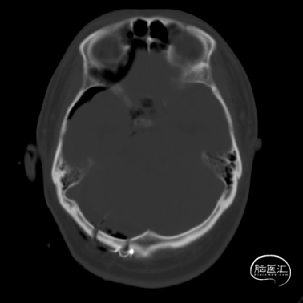

术前MRI检查提示左侧丘脑中脑海绵状血管瘤并卒中,梗阻性脑积水;

诊断:1.左侧丘脑中脑海绵状血管瘤并卒中,2.梗阻性脑积水;

年轻患者,较短时间内发生左侧丘脑二次出血,出现右侧面部及上肢麻木,复视,第二次出血后并发梗阻性脑积水,出现头痛。结合病史、神经系统体征、头颅CT及MRI检查,诊断左侧丘脑及中脑CM并卒中、脑积水明确,并导致了神经功能障碍,具备手术指征。

脑积水导致的颅内高压,幕下小脑上通路更为狭小,大脑大静脉复合体的显露及分离困难增大;